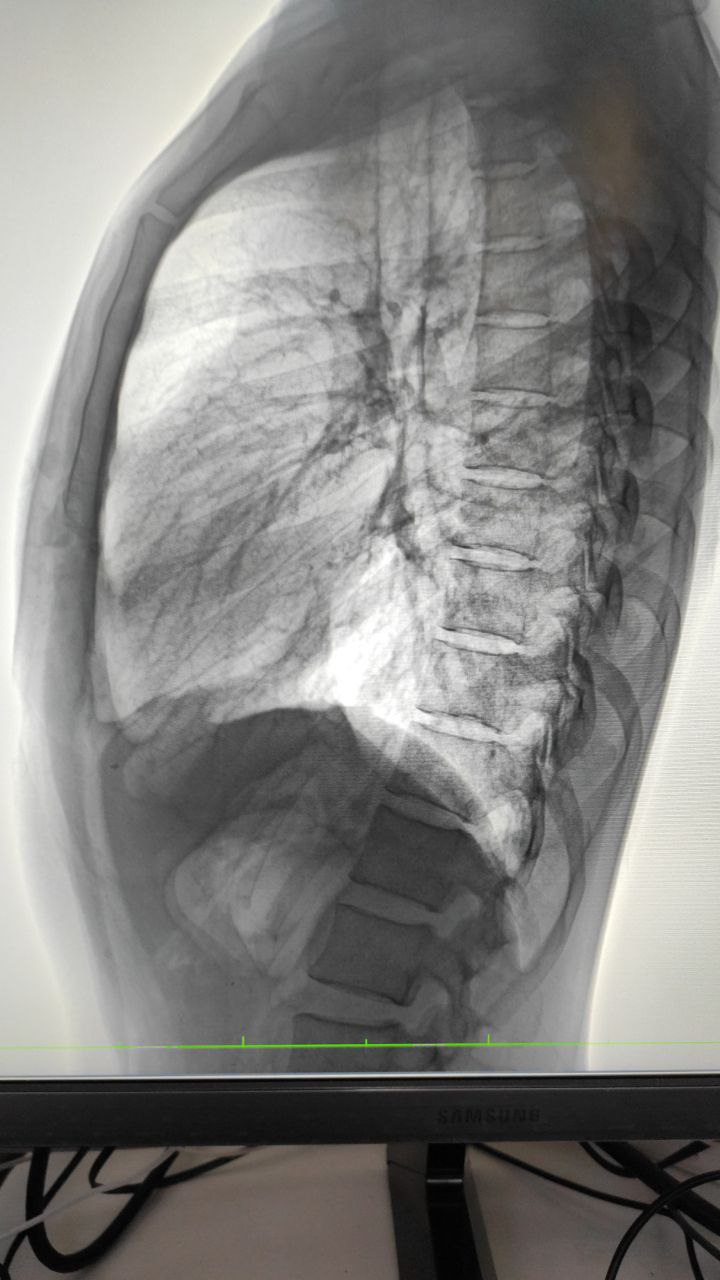

Добрый день. Татьяна. Хотела проконсультироваться по снимку. Обнаружили ковид .вдруг воспаление.. Хотела  уточнить.. Но я так понимаю тут чат для медиков. Уж простите, что внедрилась. Возможно кто-то поможет.